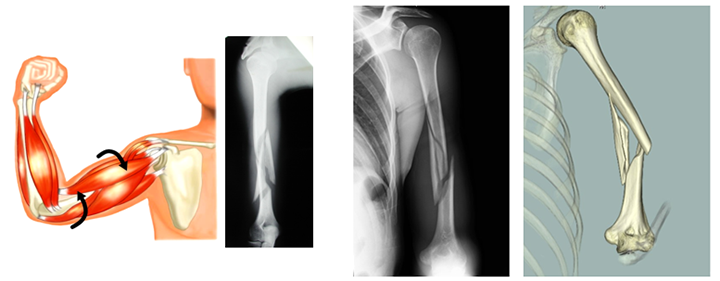

上腕とはいわゆる「二の腕」のことです。

上腕骨は肩と肘の間をつなぐ骨であり、骨幹部とはその中央部付近を指します。

上腕骨骨幹部骨折の多くは交通事故や転落などによって直接的な外力が加わったり、投球動作や腕相撲のように大きな捻じる力が瞬間的に加わることで発生します。

投球骨折・腕相撲骨折→らせん状の骨折になります